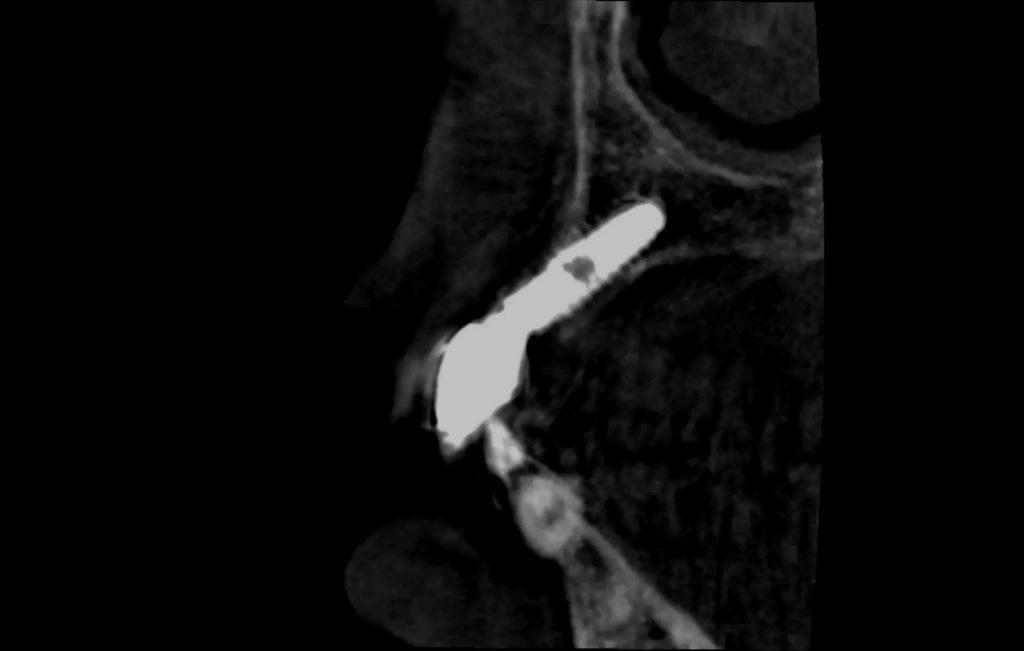

Периапикальные рентгенограммы показали контакт кости с мезиальной и дистальной сторонами имплантата. Однако клиническое исследование и КЛКТ выявили потерю лабиальной и небной костной массы, что свидетельствует о неправильном расположении имплантата (фото 2).

Фото 2: КЛКТ свидетельствует о неправильном расположении лабиального имплантата и потере костной массы.